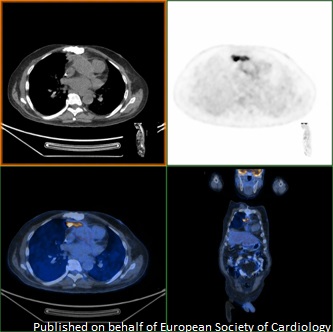

Would you use pursue FDG PET-CT scanning for suspected prosthetic valve endocarditis with negative cultures, TTE and TEE? bit.ly/38pxdxc Mohammed Ali European Society of Cardiology #echofirst #openaccess #EHJCaseReports #ESCCoT #ESCardioEd #CardioTwitter #MedTwitter

Would you use pursue FDG PET-CT scanning for suspected prosthetic valve endocarditis with negative cultures, TTE and TEE? bit.ly/38pxdxc